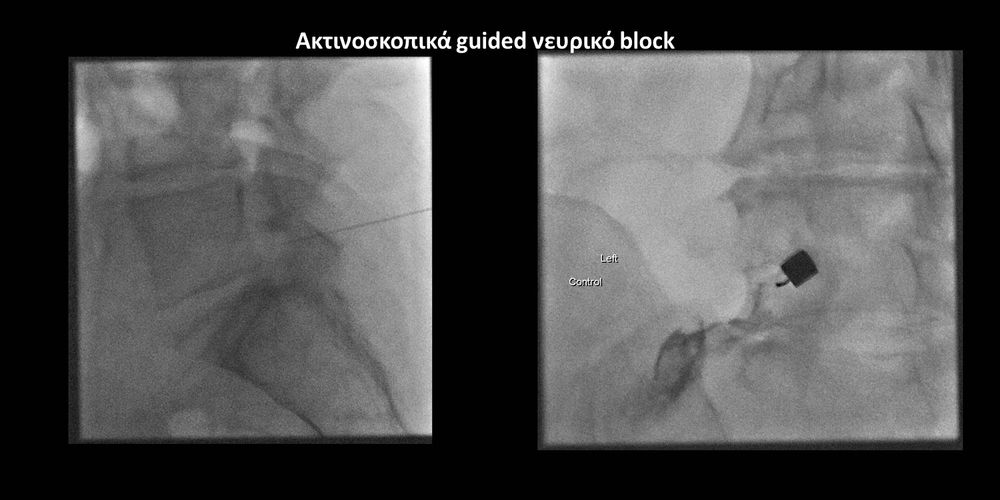

Με την βοήθεια της επεμβατικής ακτινολογίας είναι δυνατόν να πραγματοποιηθούν διαφορες ενέσιμες τεχνικές που αποσκοπούν στη μείωση του μυοσκελετικού πόνου, την ενίσχυση της αποτελεσματικότητας της φυσιοθεραπείας και την επιτάχυνση της διαδικασίας επούλωσης. Οι τεχνικές αυτές περιλαμβάνουν την κατευθυνόμενη έγχυση φαρμάκων ή πραγματοποίηση θεραπευτικών χειρισμών ακριβώς στη θέση τηςπαθολογία. Ετσι εξασφαλιζεται η μέγιστη αποτελεσματικότητα ( έως 95% κατά περίπτωση) και ασφάλεια σε σχέση με τυφλούς χειρισμούς χωρίς ακτινολογική καθοδήγηση.